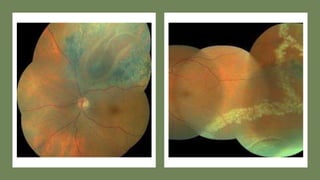

Diabetic retinopathy

Pan retinal

photocoagulatio

n

⚫Super quad will provide wider

field of view and adequate

magnification

⚫Gonio Solis used to hold in

position

⚫Superior control of patient eye

movements

PRP laser